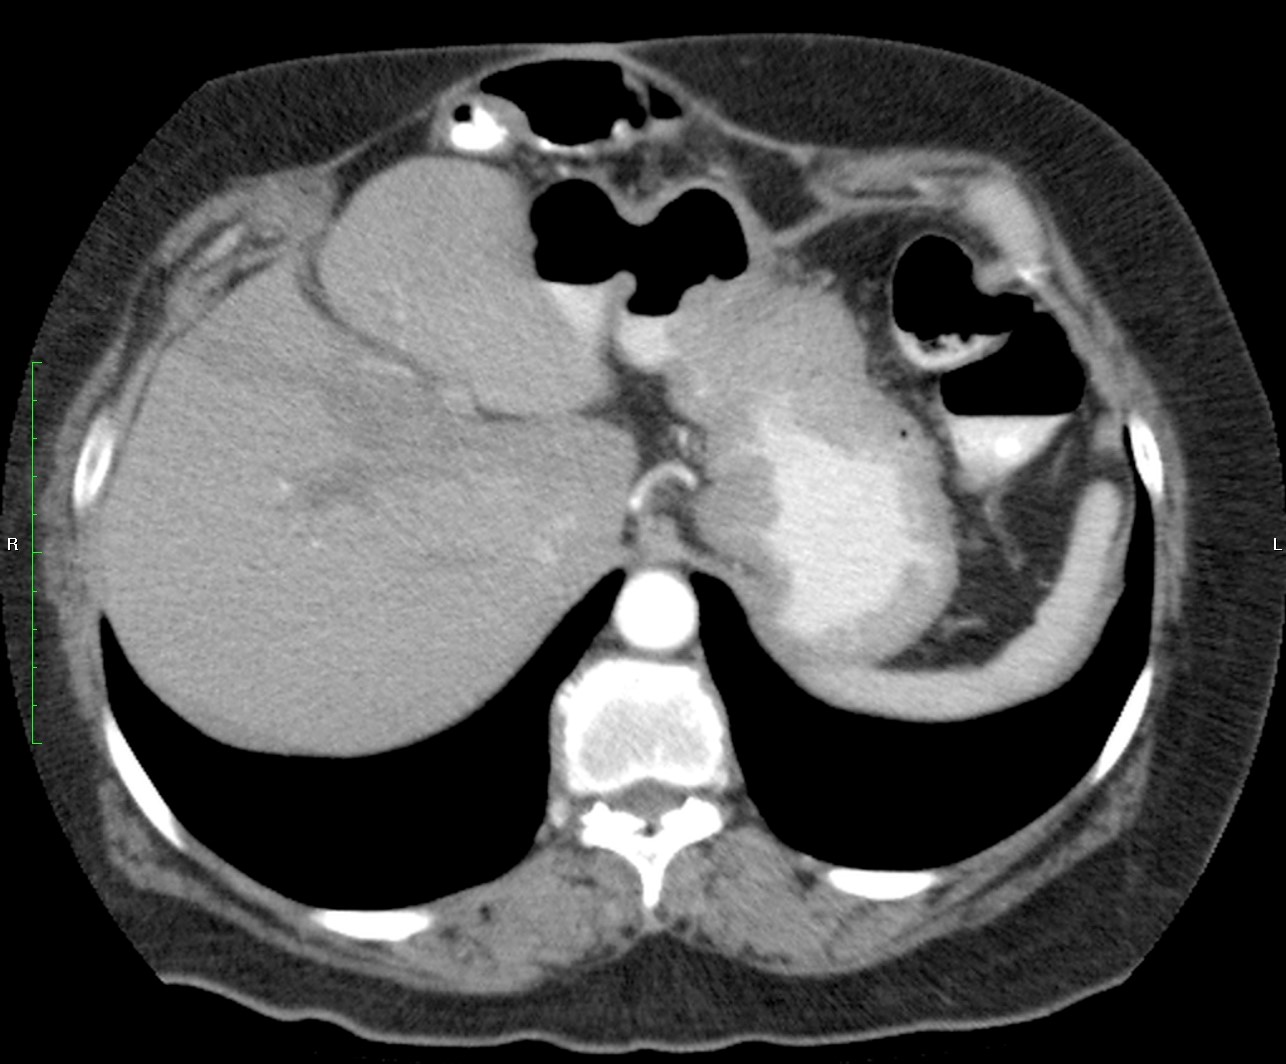

Mujer de 57 años.

Cuadro clínico de 1 mes de evolución caracterizado por distensión abdominal e hiporexia.